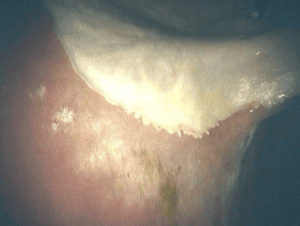

Normal Lesser Curvature

Normal Pylorus / Stomach Exit